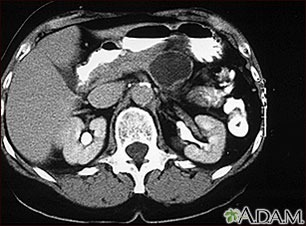

Pancreatic, cystic adenoma - CT scan

A CT scan of the upper abdomen showing a large cyst in the pancreas (cystic adenoma of the pancreas) seen on the upper right side of the picture.